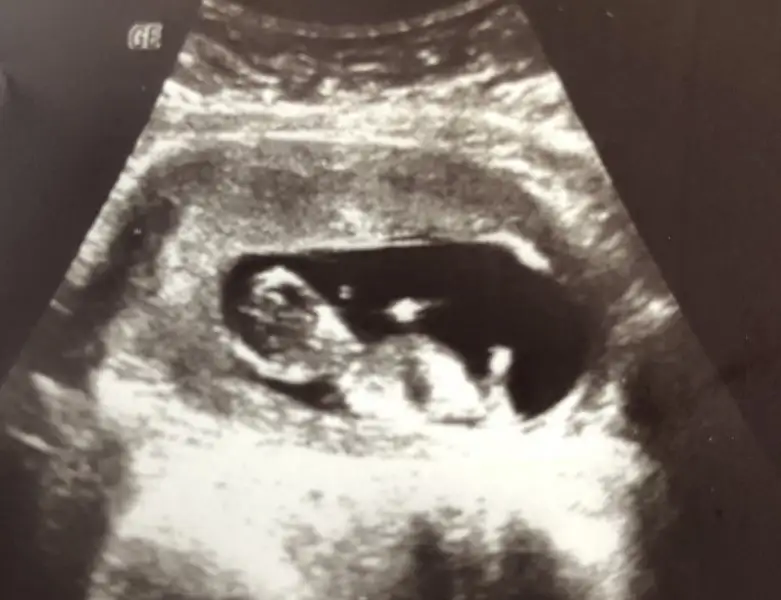

Düşüncesizler ya olumsuz düşünme canım neşelenki bebişinde içerde neşelensin inşallah :) maşallah güzel haberler için canım çok sevindim adınaBulantılar artık sabaha düştü kuzum. Tokken sıkıntım yok. Ama dün bir düğüne katıldık orda aniden dibimde konfeti patlattılar aklım çıktı çok korktum ondan sonra kasıklarım kasıldı sürekli çok ağrım oldu dün gece. Allahtan bugün kontrol günümdü doktor hiç kalkmadan yatman lazım dedi düşük tehdidi olabilir dedi. Aniden olunca çok korktum maalesef. Onun dışında enfeksiyon geçmiş kan değerlerimde hiç sıkıntı yok. Folik asiti bıraktık folat değeri çok yüksek çıktı decavite ve coledana başladık içinde biraz folik asit varmış o sana yeter dedi. Bebek sata göre 11+5 ama 12+2 çıktı ikili test yaptık. Ensesini ölçmek için uyandırmaya çalıştı baya sıpam uyanmadı bir türlü uğraştı baya uyandı sonra elini yüzüne kapattı sürekli kocaman olmuş :) büyük ihtimalle erkek çünkü pipisini bende gördümbende durumlar böyle o iyi olsunda bulantılara da razıyım çok telaşlandım ağladım iyi çok şükür. Rabbim sağlıkla biran evvel doğurmak nasip etsin hepimize